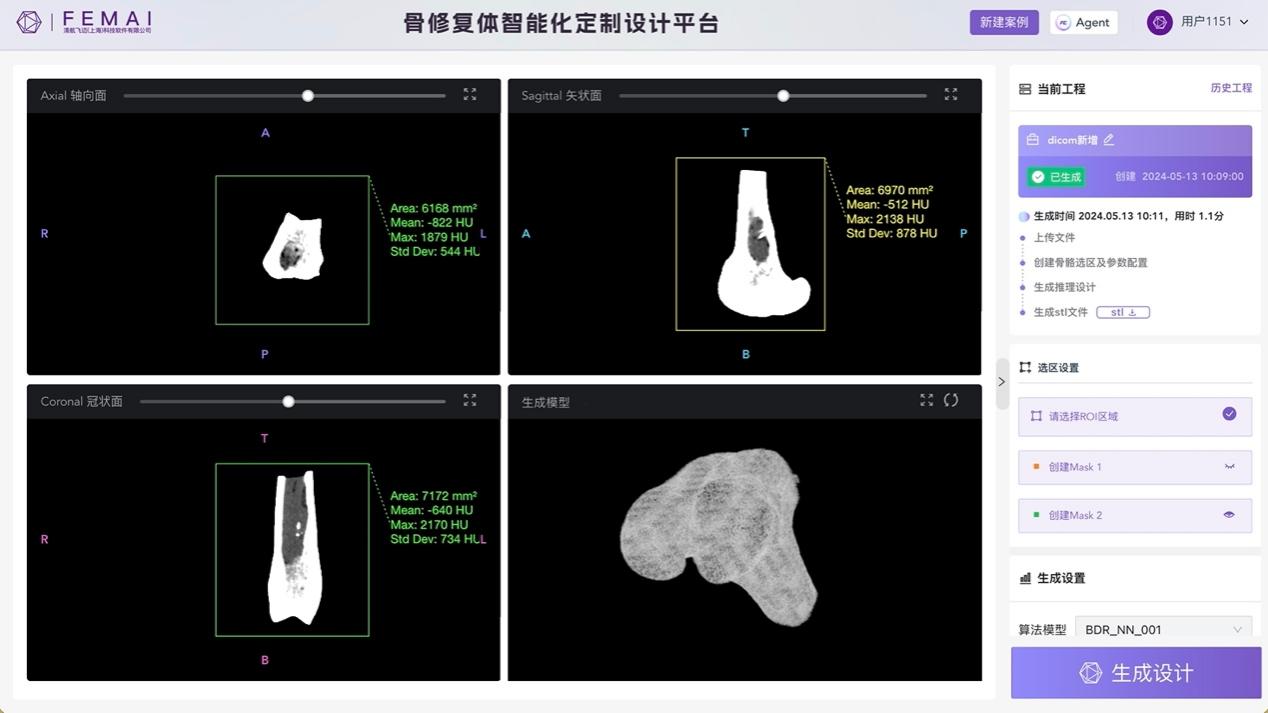

图3 在完成设计后直接输出可供制造端使用的3D打印假体骨点阵文件

3.端到端生成重塑业界诊疗新范式

该成果通过智能化设计,实现骨修复体定制设计的高度自动化,极大降低了目前个性化骨修复体定制流程中的人工参与度,推动医院方、设计方、制造方交流机制从串联式点对点信息传递向端到端有机协同运管迭代。